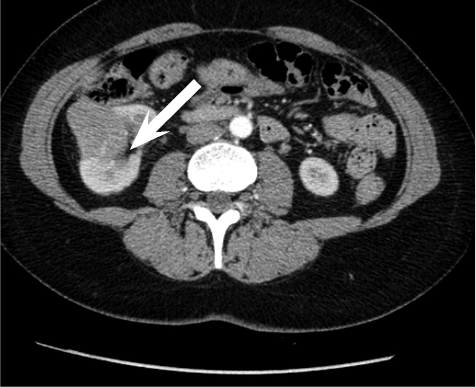

Figure 5. Pseudoaneurysm embolized using 3 coils

Pseudoaneurysm was embolized with two 8 mm x 20 cm coils, an additional coil of 12 mm x 30 cm (Figure 5).

Control angiography with contrast was performed. Pseudoaneurysm was completely occluded and no longer visible (Figure 6). No extravasation was found.

After embolization, creatinine decreased till 83 µmoL/L and eGFR was 73 mL/min/1.73 m2. Pseudo­aneurysm was no longer visible, as well as small segmental branches. Vascularization of renal parenchyma is reduced.